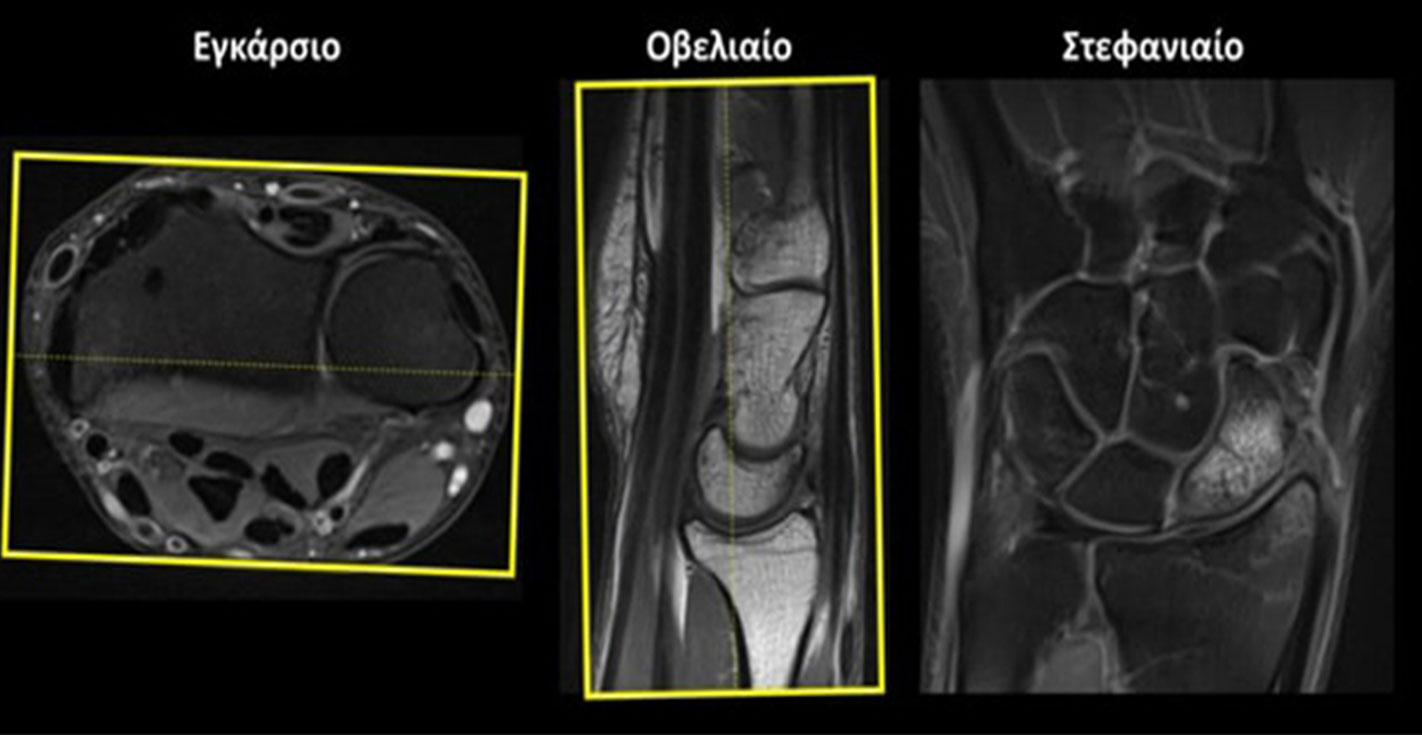

Στεφανιαίο (Coronal): οι στεφανιαίες τομές σχεδιάζονται παράλληλα με τη νοητή γραμμή που ενώνει τη στυλοειδή απόφυση της κερκίδας και της ωλένης στο εγκάρσιο επίπεδο και κάθετα στην ΠΧΚ άρθρωση στο οβελιαίο επίπεδο. Οι τομές πρέπει να περιλαμβάνουν ολόκληρη την ΠΧΚ άρθρωση από μπροστά έως πίσω.

Εγκάρσιο (Axial/Transversal): οι εγκάρσιες τομές σχεδιάζονται παράλληλα με τη ΠXΚ άρθρωση τόσο στο στεφανιαίο όσο και στο οβελιαίο επίπεδο. Οι τομές πρέπει να περιλαμβάνουν ολόκληρη την ΠΧΚ άρθρωση από πάνω έως κάτω.

Οβελιαίο (Sagittal):οι οβελιαίες τομές σχεδιάζονται κάθετα στη νοητή γραμμή που ενώνει τη στυλοειδή απόφυση της κερκίδας και της ωλένης στο εγκάρσιο επίπεδο και κάθετα στην ΠΧΚ άρθρωση στο στεφανιαίο επίπεδο. Οι τομές πρέπει να περιλαμβάνουν όλα τα οστά του καρπού από έσω προς τα μέσα.